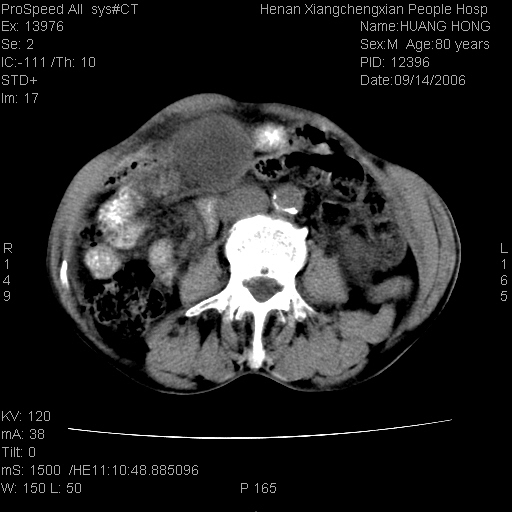

患者, 男, 80岁, 发现上腹部包块1年余,无其它不适.2006-9-14ct片是喝水后扫描2006-9-15ct片没喝水扫描![]() ![]() ![]() ![]() ![]() ![]() ![]() ![]() ![]() ![]() ![]() ![]() ![]() ![]() ![]() ![]() 以上是喝水片 以下是空腹片 ![]() ![]() ![]() ![]() ![]() ![]() ![]() ![]() ![]() ![]() ![]() ![]() ct:胰腺前方、肝脏与胃之间可见巨大类圆形囊性低密度影,大小约152mmx145mmx118mm,上缘平t11椎体上缘,下缘平l3椎体下缘,密度均匀,ct值15hu,其内呈多房分隔,囊壁薄且光滑,边界清晰,周围组织及器官明显受压。肝脏实质内未见异常密度影,胆囊未见异常,胰腺密度未见异常,脾脏大小、形态及密度未见异常,腹膜后间隙未见肿大淋巴结影。 印象:胰腺前方、肝脏与胃之间巨大类圆形囊性低密度影.性质待定。多考虑:.肠系膜巨大囊肿。 守望可可西里发言:支持楼主,考虑肠系膜囊肿,多为小肠系膜。 ysxyy发言:我总觉得这个病人虽然很像肠系膜囊肿,但还是应该强化一下; 下面这几幅图里肿块和主动脉的关系不太清,不知能否除外血管性来源? ![]() ![]() ![]() 病理结果:横结肠系膜间叶瘤.部分区域间质细胞增生活跃. 病理图片 ![]() 良性间叶瘤:是指由两种或两种以上的间叶组织所构成的混合性肿瘤.肿瘤仅发生在腹膜后和肠系膜,.前者较后者多发.良性间叶瘤常发生在肾或四肢,腹膜后较少见,各年龄均可发病.女多与男,预后较好,但术后易复法. 恶性间叶瘤:由两种以上恶性间叶组织成分组成. 光镜:肿瘤由脂肪/血管/平滑肌构成. 原贴地址: http://www.radinet.com.cn/forum_view.asp?forum_id=4&view_id=16217 ok |